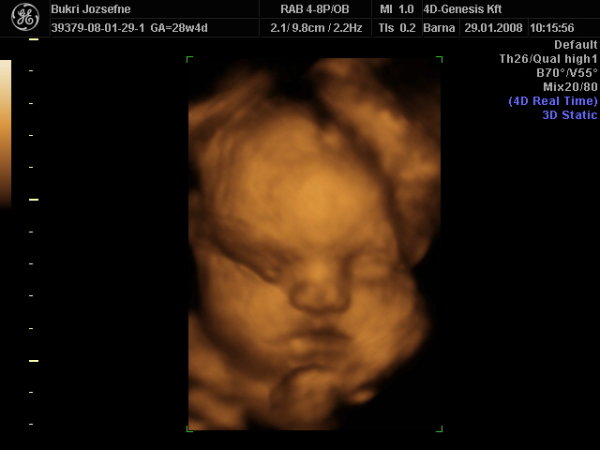

A doki szerint pufók kislány